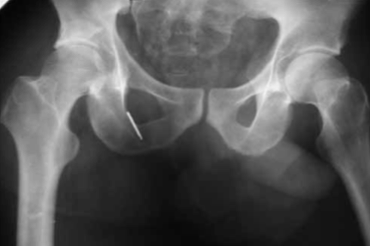

Для ранней активизации больного операция заканчивается установкой аппарата внешней фиксации. Аппарат позволяет гарантированно стабилизировать тазобедренный сустав с заданной или регулируемой разгрузкой, что создает условия не только для срастания перелома, но и для расправления или восполнения участков импрессии или компрессии с восстановлением структуры субхондрального слоя (рис. 2, 3).

Обзорная рентгенограмма таза. Состояние после открытой репозиции и фиксации верхнего отдела заднего края вертлужной впадины винтом. Стабилизация и разгрузка тазобедренного сустава в аппарате внешней фиксации

Рентгенография тазобедренного сустава в двух проекциях (прямая и аксиальная). Срок после оперативного лечения — 6 лет